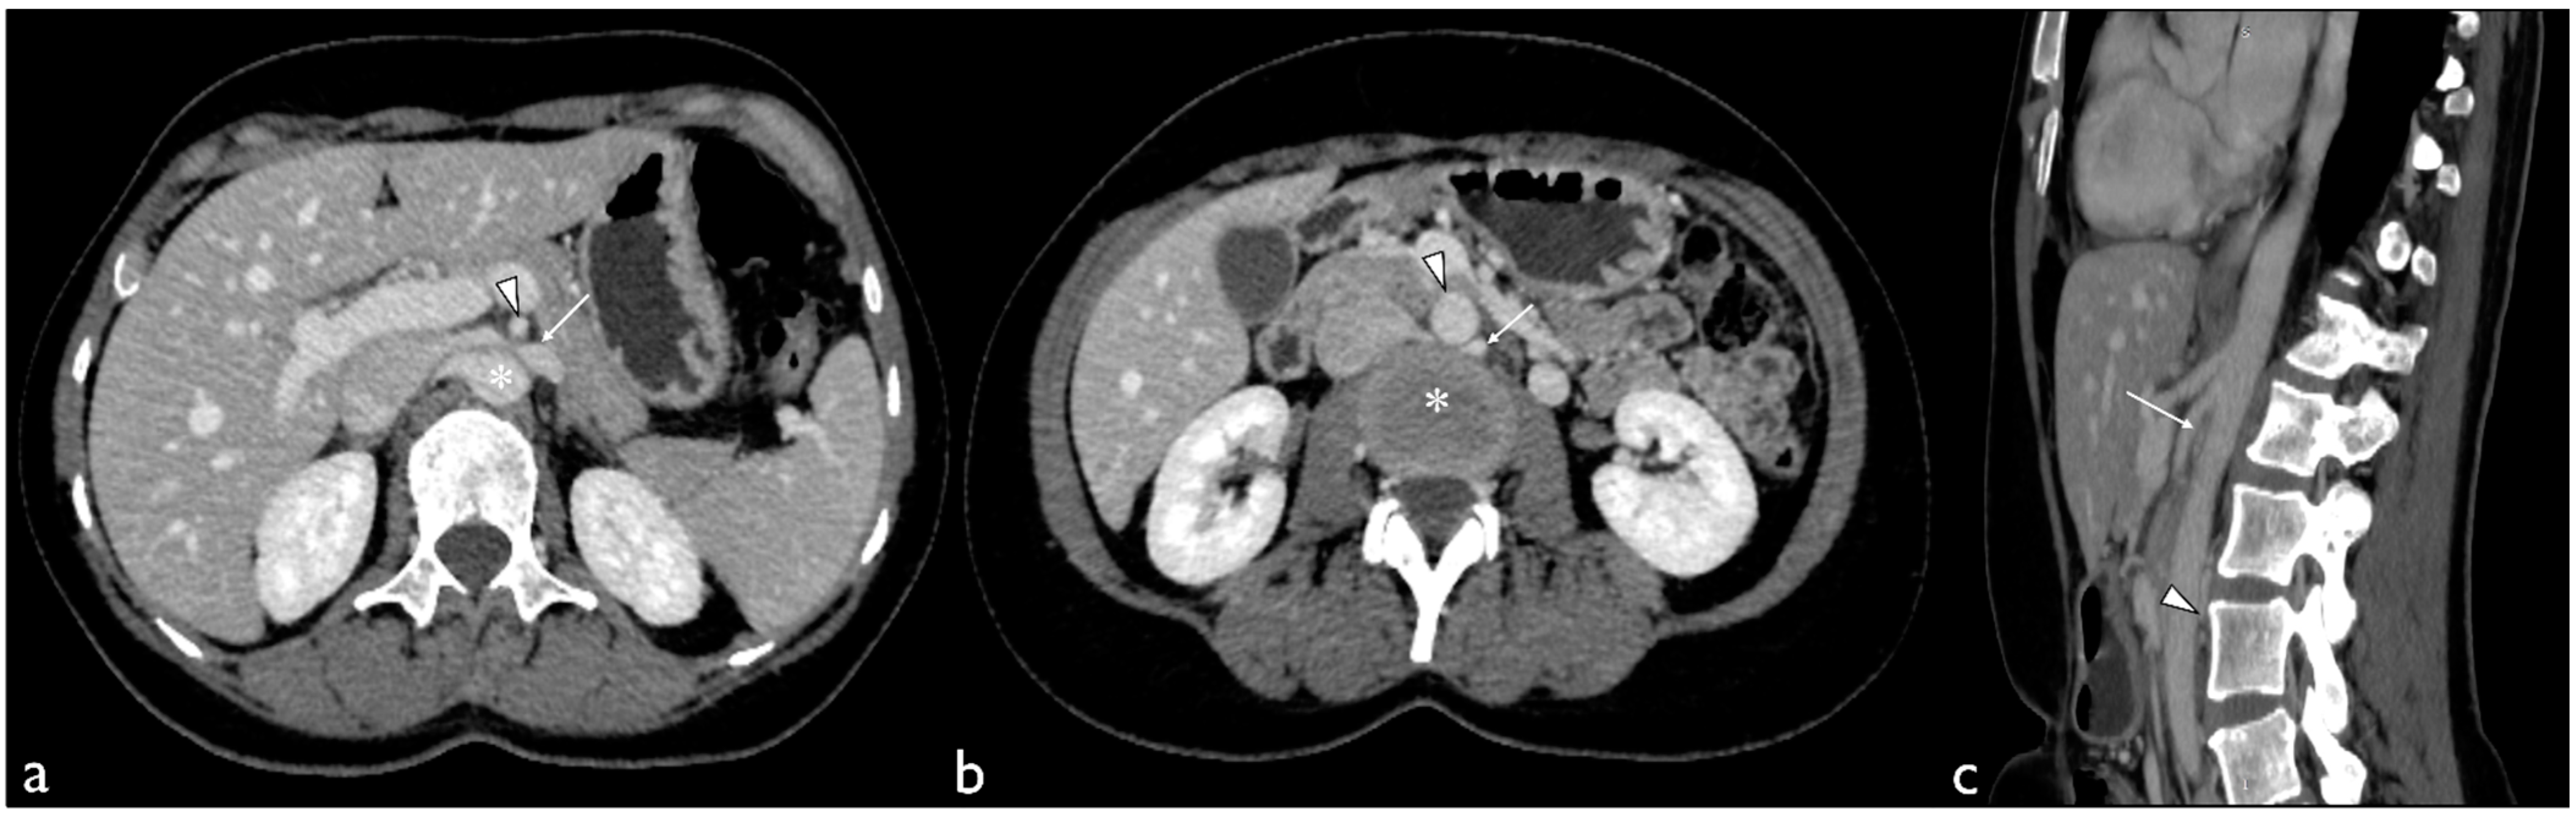

2. Case Presentation